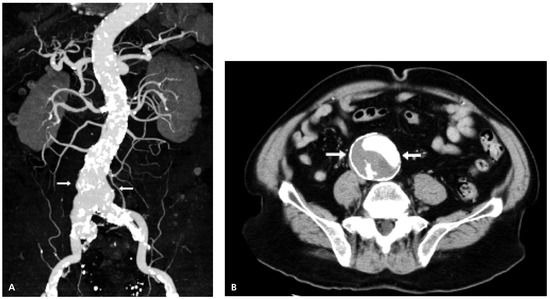

Severe Coronary Artery Ectasia and Abdominal Aortic Aneurysm

by Ruth von Dahlen, Stephanie Kiencke, Christoph Kaiser and Peter Rickenbacher

Cardiovasc. Med. 2006, 9(10), 348; https://doi.org/10.4414/cvm.2006.01199 - 27 Oct 2006

Cited by 1 | Viewed by 118

Coronary artery ectasia (CAE), a discrete or fusiform arterial dilatation, is an uncommon angiographic finding. We report the case of a patient presenting with an acute coronary syndrome in whom further evaluation revealed coronary artery disease with severe CAE in the presence of [...] Read more.

Coronary artery ectasia (CAE), a discrete or fusiform arterial dilatation, is an uncommon angiographic finding. We report the case of a patient presenting with an acute coronary syndrome in whom further evaluation revealed coronary artery disease with severe CAE in the presence of an abdominal aortic aneurysm (AAA). Since both entities are strongly associated with local and systemic atherosclerosis, they have traditionally been viewed as a variant of atherosclerosis. The combined occurrence of CAE and AAA, as in the present case, raises questions about common pathogenetic mechanisms apart from atherosclerosis. The respective evidence will be reviewed. Full article